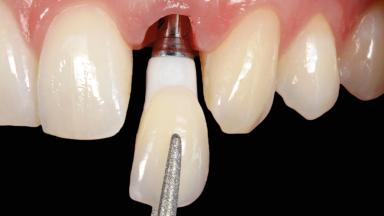

In this case, Arndt Happe describes how he achieved a stable outcome at 5 years by giving careful attention to the coronal aspect of the transmucosal area of the provisional, creating a slim emergence profile.